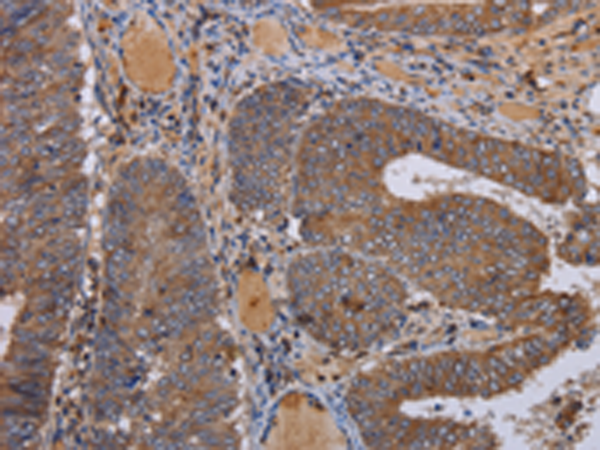

分类: 科研抗体货号: P08310别名: MTVR1应用: WB,IHC反应种属: Human, Mouse